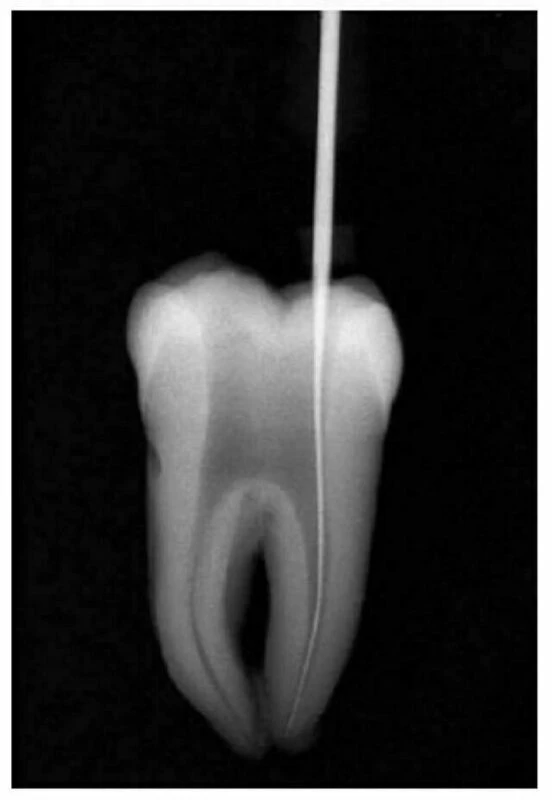

3) Dễ dàng đưa dụng cụ vào ống tủy

Sàn tủy những răng sau có những rãnh không những giúp tìm miệng ống tủy mà còn hướng dẫn để đưa dụng cụ vào. Sàn tủy thường lồi và tạo nên một góc nhọn với các thành buồng tủy. Vì vậy nếu xoang tủy làm tốt, nhất là khi sàn tủy không bị cắt bởi mũi khoan, dụng cụ sẽ được đưa vào dễ dàng mà không gặp phải bất kỳ trở ngại nào. Dụng cụ có thể trượt dọc theo thành này và hướng đến miệng ống tủy. Các thành sẽ được sửa soạn bởi các nhà nội nha, còn sàn tủy được tự nhiên tạo ra để hướng dụng cụ vào đến chóp chân răng (hình 11.5).

Hình 11.5. Xoang tủy ở răng cối thứ nhất hàm dưới. Độ lồi của sàn tủy hướng dẫn cho dụng cụ đến miệng ống tủy

Không nên để dụng cụ nội nha bị làm kẹt lại bởi thân răng. Khi làm việc ở ống tủy, chúng phải được di chuyển thoải mái, nhất là ở 1/3 chóp (hình 11.6).